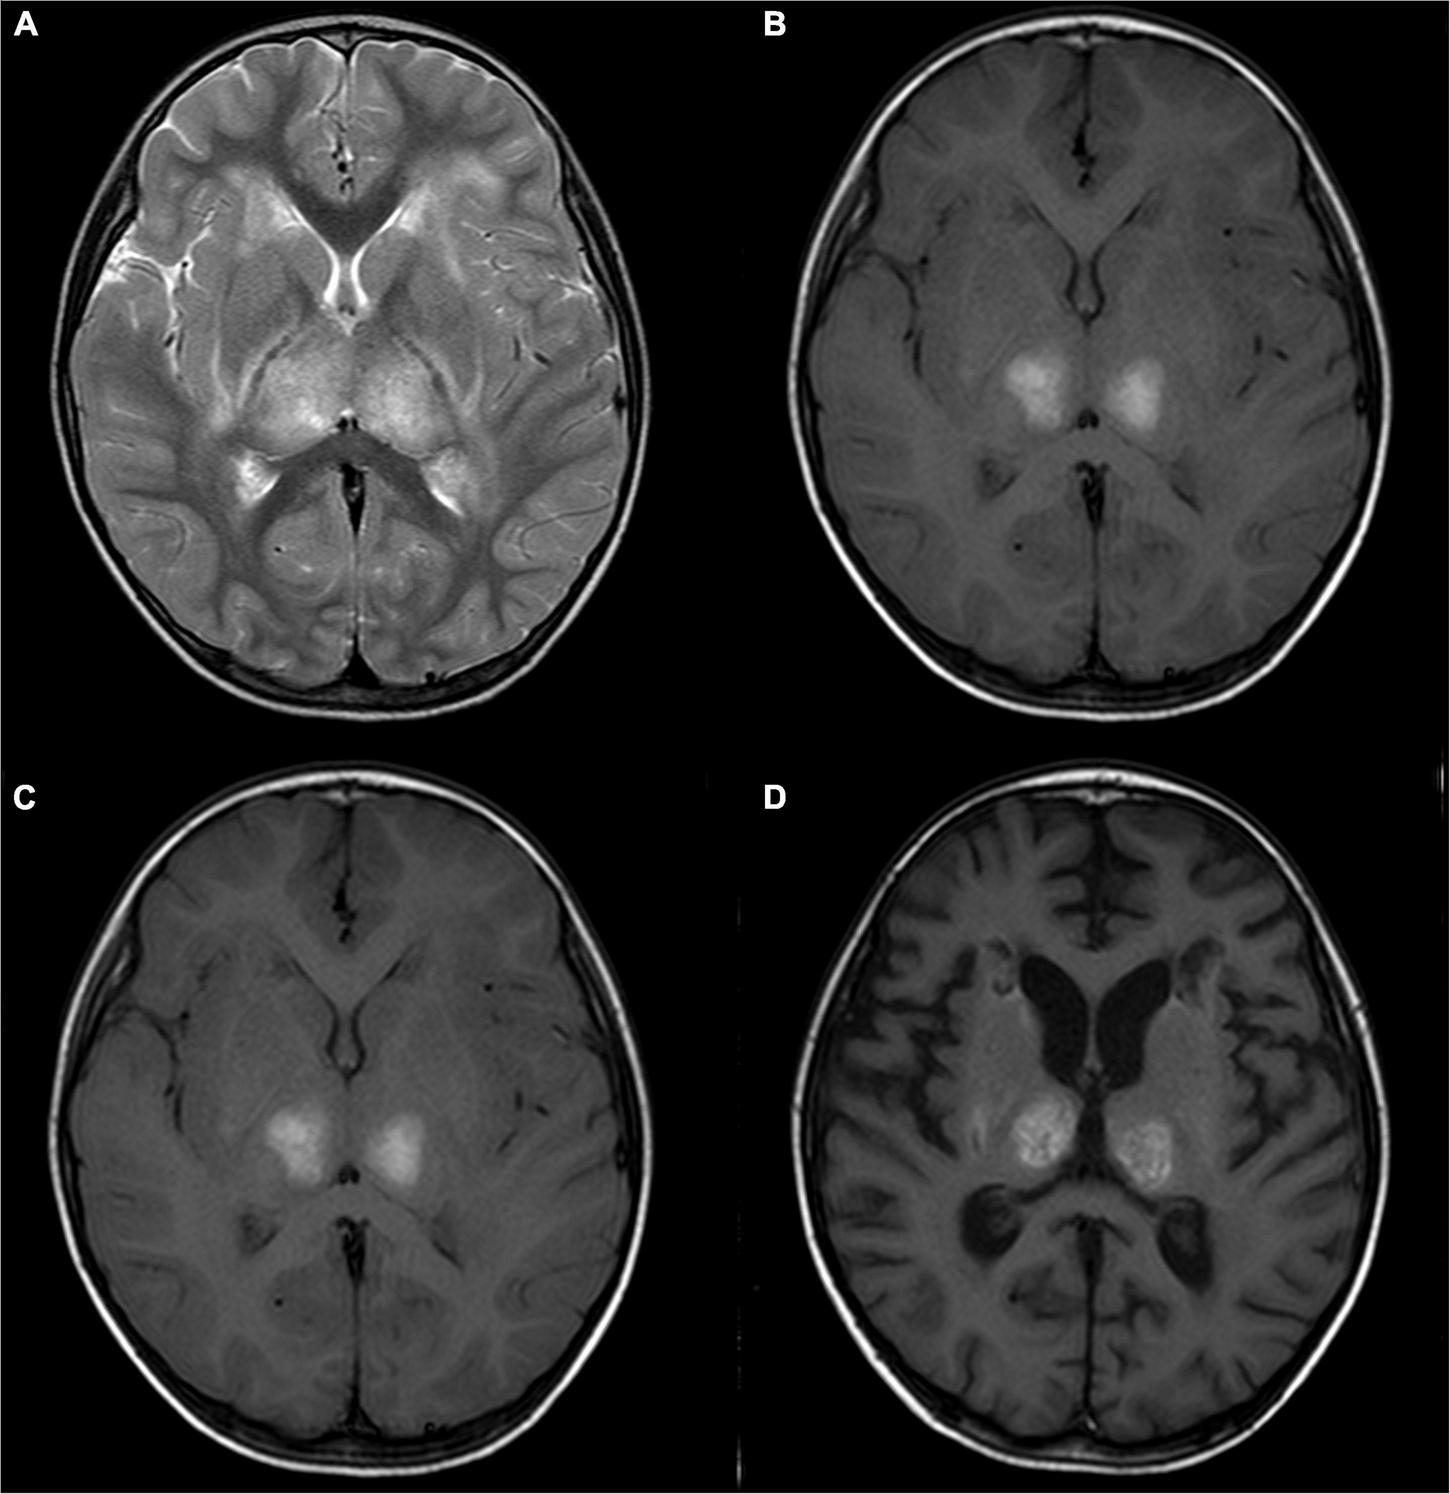

A 2-year-old girl with acute necrotizing encephalopathy, with fever and seizure. (A) T2WI shows slightly high symmetrical signals in the bilateral thalamus. (B) T1WI shows symmetrical hyperintensity in the bilateral thalamus. (C) One month later, T2WI shows irregular high signal in bilateral thalamus. (D) One month later, T1WI shows irregular high signal in bilateral thalamus.

The BAEP, EEG, and brain MRI anomaly rates were 81.8, 100, and 100%, respectively. Eleven pediatric patients underwent BAEP examination, and normal values were found in two children, and mild abnormalities were noted in nine children (showing prolongation of wave I–V latency). Ten (83.3%) pediatric patients showed diffuse slow waves on EEG and two (16.7%) showed asynchronous spike waves. Brain MRI displayed symmetric necrosis of the thalamus and other deep brain structures, particularly in the brain stem, peripheral white matter, and cerebellar medulla. All ANE children had thalamus lesions accompanied by cerebral and/or cerebellar lesions. Seven children (58.3%), including the non-survivors, developed brain stem lesions (Figures 1, 2 and Table 3). Eleven children underwent MRI more than twice, with a median interval of 116 days (IQR: 33, 273). Lesions with cavitation were found in five cases during follow-up. MRI score-I ranged from 1 to 3 (1.8 ± 0.7) points based on the initial scan. MRI score-II varied from 1 to 4 (2.5 ± 1.1) points based on the initial and follow-up scans. ANE-SS ranged from 1 to 6 (3.9 ± 1.3) points. The scores of mRS were from 0 to 6 (2.9 ± 1.7) points.